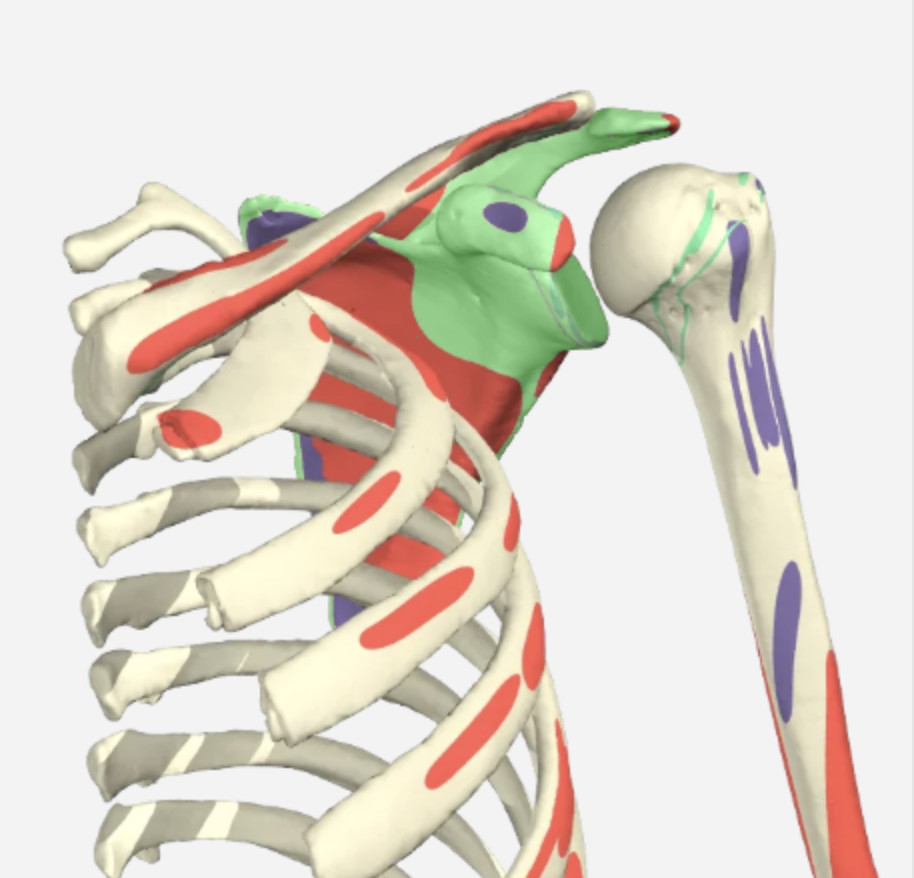

肩痛:保守治疗的有效性

参考文献:Steuri, R.、Sattelmayer, M.、Elsig, S.、Kolly, C.、Tal, A.、Taeymans, J. 和 Hilfiker, R. (2017)。保守干预措施(包括运动、手法治疗)的有效性......